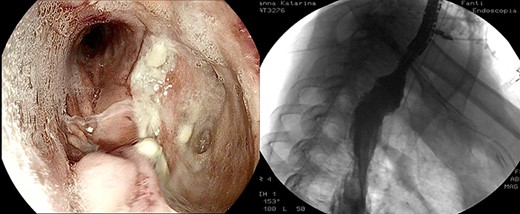

Large anastomotic leakage after minimally invasive esophagectomy opening to a cavity in the pleural space of 8 cm in size.

On the third postoperative day (POD), inflammatory indexes increased (CRP 178.2 ng/mL). On the fourth POD, the endoscopy and CT scan showed a large anastomotic leak involving 75% of the anastomosis and opening to a giant wound cavity in the pleural space of 8 cm in size; fibrosis and abundant necrotic tissue were also present (Fig. 1).